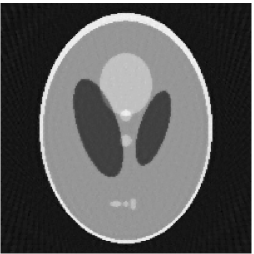

Furthermore, we used the classic ART iteration as the iteration operator in our numerical experiments. In order to compare the proposed superiorization algorithm with the classic superiorization algorithm, we applied the classic superiorization and -PP superiorization algorithm to two phantoms (see figure 1). The first one is the Shepp-Logan phantom[30], and the second one is the head phantom with a ghost which is invisible at 22 specified projection directions [10, 31]. In addition, we compare the performances of the two algorithms for the noiseless and noised data with different projections. In all experiments, the noised projection data was corrupted by additive Gaussian white noise with variance . We record the iterations, running time of program and mean square error (MSE) of different algorithms, where MSE is computed by

Noiseless projection data: Since the ghost in this phantom is invisible at 22 directions [10, 11], the reconstruction images usually suffer from artifacts. in our simulations, the projection data were collected in 112 and 82 directions: 90 and 60 with equal angle increments from to and 22 specified views in which the ghost is invisible [10]. Iteration procedures were terminated when for the noiseless projections.

The reconstruction images from the noiseless projection data were shown in the Fig. 6. For comparison, Table 3 present the iterations, MSE, Res and running time(RT) of different reconstruction results.